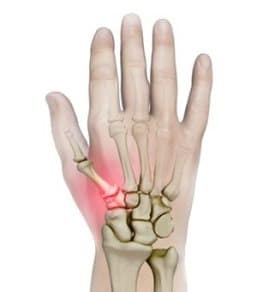

Wrist Fractures

Wrist Scaphoid Fractures

Carpal Injuries

Wrist Scaphoid Nonunion